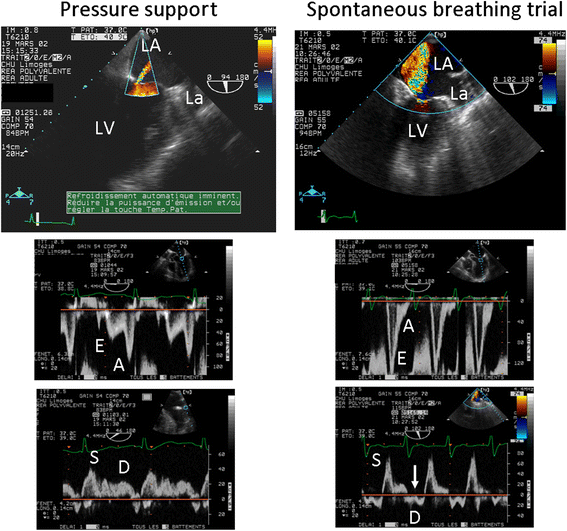

Acute respiratory failure (ARF) is a leading indication for performing critical care ultrasonography (CCUS) which, in these patients, combines critical care echocardiography (CCE) and chest ultrasonography. CCE is ideally suited to guide the diagnostic work-up in patients presenting with ARF since it allows the assessment of left ventricular filling pressure and pulmonary artery pressure, and the identification of a potential underlying cardiopathy. In addition, CCE precisely depicts the consequences of pulmonary vascular lesions on right ventricular function and helps in adjusting the ventilator settings in patients sustaining moderate-to-severe acute respiratory distress syndrome. Similarly, CCE helps in identifying patients at high risk of ventilator weaning failure, depicts the mechanisms of weaning pulmonary edema in those patients who fail a spontaneous breathing trial, and guides tailored therapeutic strategy. In all these clinical settings, CCE provides unparalleled information on both the efficacy and tolerance of therapeutic changes. Chest ultrasonography provides further insights into pleural and lung abnormalities associated with ARF, irrespective of its origin. It also allows the assessment of the effects of treatment on lung aeration or pleural effusions. The major limitation of lung ultrasonography is that it is currently based on a qualitative approach in the absence of standardized quantification parameters. CCE combined with chest ultrasonography rapidly provides highly relevant information in patients sustaining ARF. A pragmatic strategy based on the serial use of CCUS for the management of patients presenting with ARF of various origins is detailed in the present manuscript.